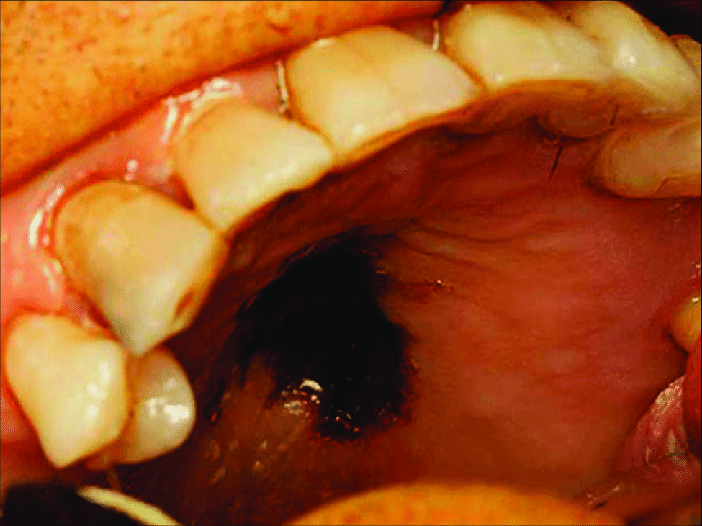

Mucormycosis of Hard Palate

The image demonstrates the fungal infection of hard palate. THis infection is also known as mucormycosis. Image via: https://www.researchgate.net/figure/Mucormycosis-affecting-the-hard-palate_fig3_324169939